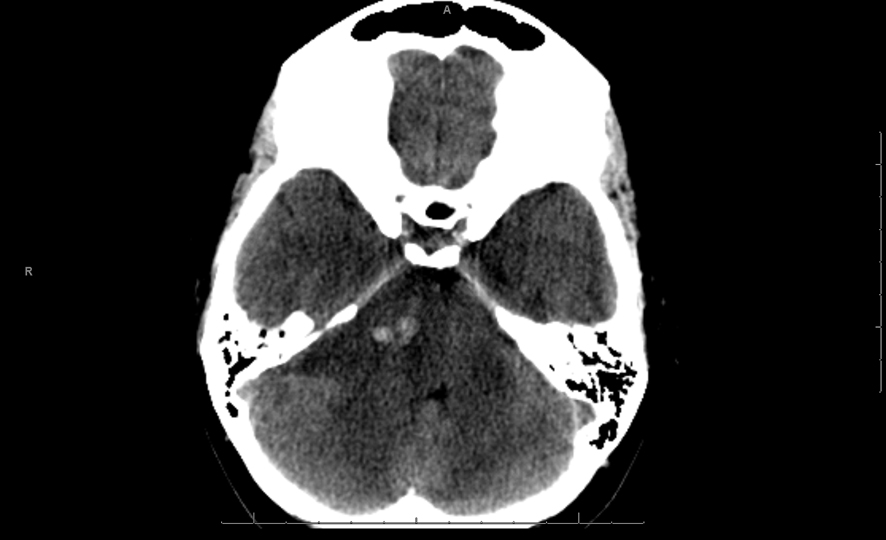

A 26 years old 30-week pregnant female initially presented for neurosurgical evaluation of an incidentally discovered right cerebellopontine (CP) angle mass. She underwent a head CT as part of routine trauma evaluation after a motor vehicle accident (Fig. 1). During her emergency room evaluation, she admitted to progressive decreased hearing in right ear with intermittent tinnitus the past several months. She also described occasional pain behind the right eye and pain along right side of the face. A non-contrast MRI confirmed a large right CP angle mass consistent with meningioma (Fig. 2a, b, c).

![]() Click for large image | Figure 1. Single axial CT image of the posterior fossa demonstrates extra-axial mass centered on the right cerebellopontine cistern. The mass is hypodense to brain parenchyma with small central hyperdense foci of acute hemorrhage. There is moderate mass effect on the adjacent pons and ipsilateral cerebellar hemisphere. |